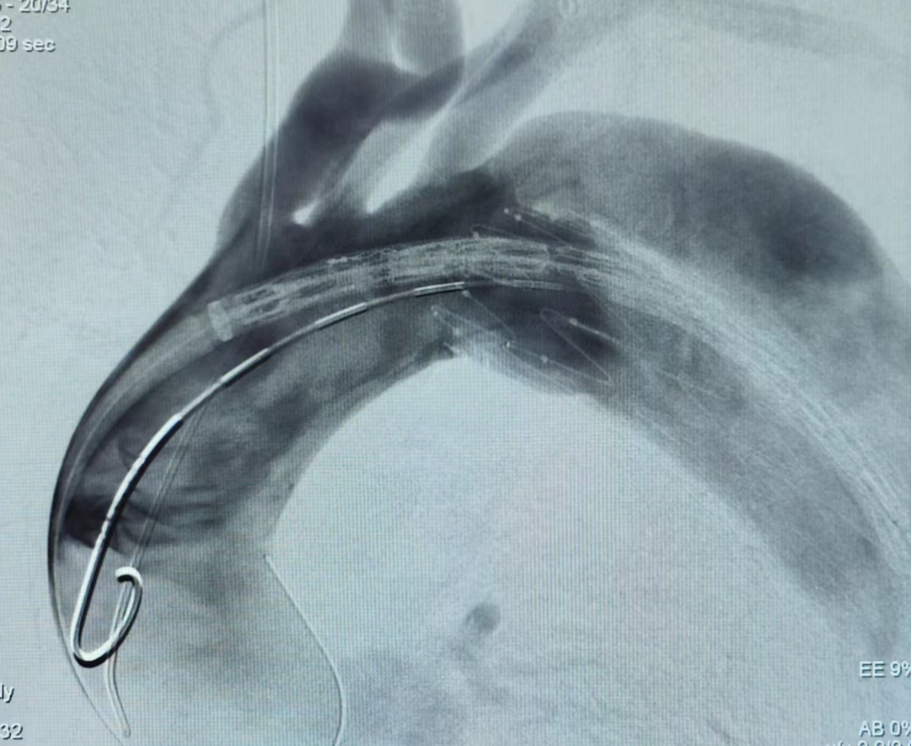

病例一(单开窗)

张XX,男,56岁,主动脉夹层。LSA单开窗。

术前

术后